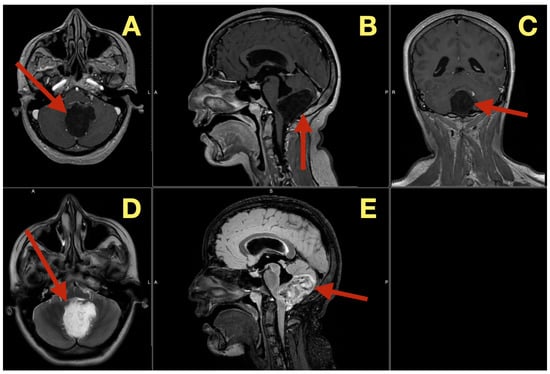

The preoperative MRI demonstrated a multilobulated mass within the fourth ventricle which was molded to the roof and cavity of the fourth ventricle. The mass arose from the inferior portion of the vermis and draped over the superior medullary velum and had smooth interfaces with the surrounding parenchyma which it displaced but did not invade. The mass was uniformly hypointense on T1 images; however, on T2/FLAIR images, the mass had hyperintensity with internal lobulation. The mass marginally compressed the uvula and nodulus and compressed the posterior surface of the pontine-medullary tegmentum. The foramen of Magendie was obliterated and both foramina of Luschka were narrowed resulting in an upstream flow void in the ventricles and a rim of periventricular interstitial edema. This created the hydrodynamic environment responsible for the patient’s symptoms. The worsening headache and vomiting in the morning, the papilledema, and nuchal rigidity resulted from the hydrodynamic environment. The avascular nature of the mass and the CSF conforming surface of the mass, as well as its central location, strongly suggested the possibility of an epidermoid cyst vs. a vascular neoplasm. The image-symptom correlation was excellent: the axial ataxia and titubation were due to compression of the fastigial nucleus and the vermian midline; the gaze-evoked nystagmus was due to disruption of the flocculonodular circuitry along the fourth ventricular roof; and the intracranial hypertension was due to obstruction of the caudal apertures. The morphology and epicenter of the mass were most consistent with a posterior fossa midline epidermoid tumor of Type 2 (fourth-ventricle epicenter) with a dominant relationship to the tela choroidea and cerebellomedullary fissure, anticipating a roof-centered growth pattern and possible focal adherence to the ventricular floor.

On the axial post contrast T1 plane (Figure 1A), the mass occupied the ventricular space like a mold, did not enhance, and was in the midline. The medial surface of the mass was in contact with the cerebellar vermis and the lateral surface of the mass slightly indented the tonsillar surfaces without penetrating into the parenchyma. On the mid sagittal T1 view (Figure 1B), the mass was in contact with the inferior vermis and caused an upward bowing of the superior medullary velum and flattening of the dorsal medulla and this explained the patient’s episodes of pressure-induced vomiting by mechanical stimulation of the area postrema. The coronal T1 reconstruction (Figure 1C) clearly demonstrated that the mass was in the midline and caused an equal compression of the two outlet recesses and was consistent with the absence of laterality in the patient’s deficits. On T2 (Figure 1D) and mid sagittal FLAIR (Figure 1E), the mass’ fluid-like appearance and internal lobulation were prominent; the surface of the mass was molded to the fourth ventricular CSF and not invading the fourth ventricular CSF, and this was a classic finding for this type of mass and accounted for the unusual severity of the fastigial/vermian hub being compressed and not destroyed.

Figure 1. Preoperative MRI of the posterior fossa. (A): Axial post-contrast T1: non-enhancing, lobulated mass centered in the fourth ventricle (arrow). (B): Mid-sagittal T1: inferior-vermis contact with upward bowing of the superior medullary velum and dorsal brainstem compression (arrow). (C): Coronal T1: strict midline localization with symmetric crowding of the ventricular outlets (arrow). (D): Axial T2: intrinsically high signal with molded margins against cerebellar tonsils (arrow). (E): Mid-sagittal FLAIR: high signal lesion with effacement of Magendie and narrowing of Luschka, concordant with obstructive hydrocephalus (arrow). Radioclinical correlation: vermian compression → truncal ataxia/titubation; flocculonodular disturbance → gaze-evoked nystagmus; outlet occlusion → intracranial hypertension.